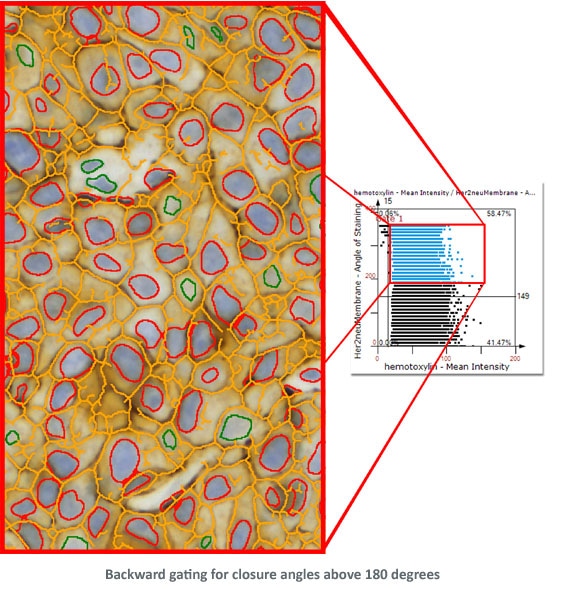

Combined with segmentation images it is also a simple and intuitive tool to visually validate results. TG calls this "Backward Gating".

The following examples show Backward Gating versatility on segmented nuclei positive for Ki-67. Backward gating can be done for any measured parameter on histograms and scattergrams.

In the second example backward gating is used to visualise cells in which the Her-2NEU staining, detected with the skeleton algorithm, has a closure angle of more than 180 degrees.

Morphological Filtering using Tissue Cytometry technology combined with appropriate planning of the analysis provides a highly flexible and capable instrument for extracting specific data from a sample (see image below).